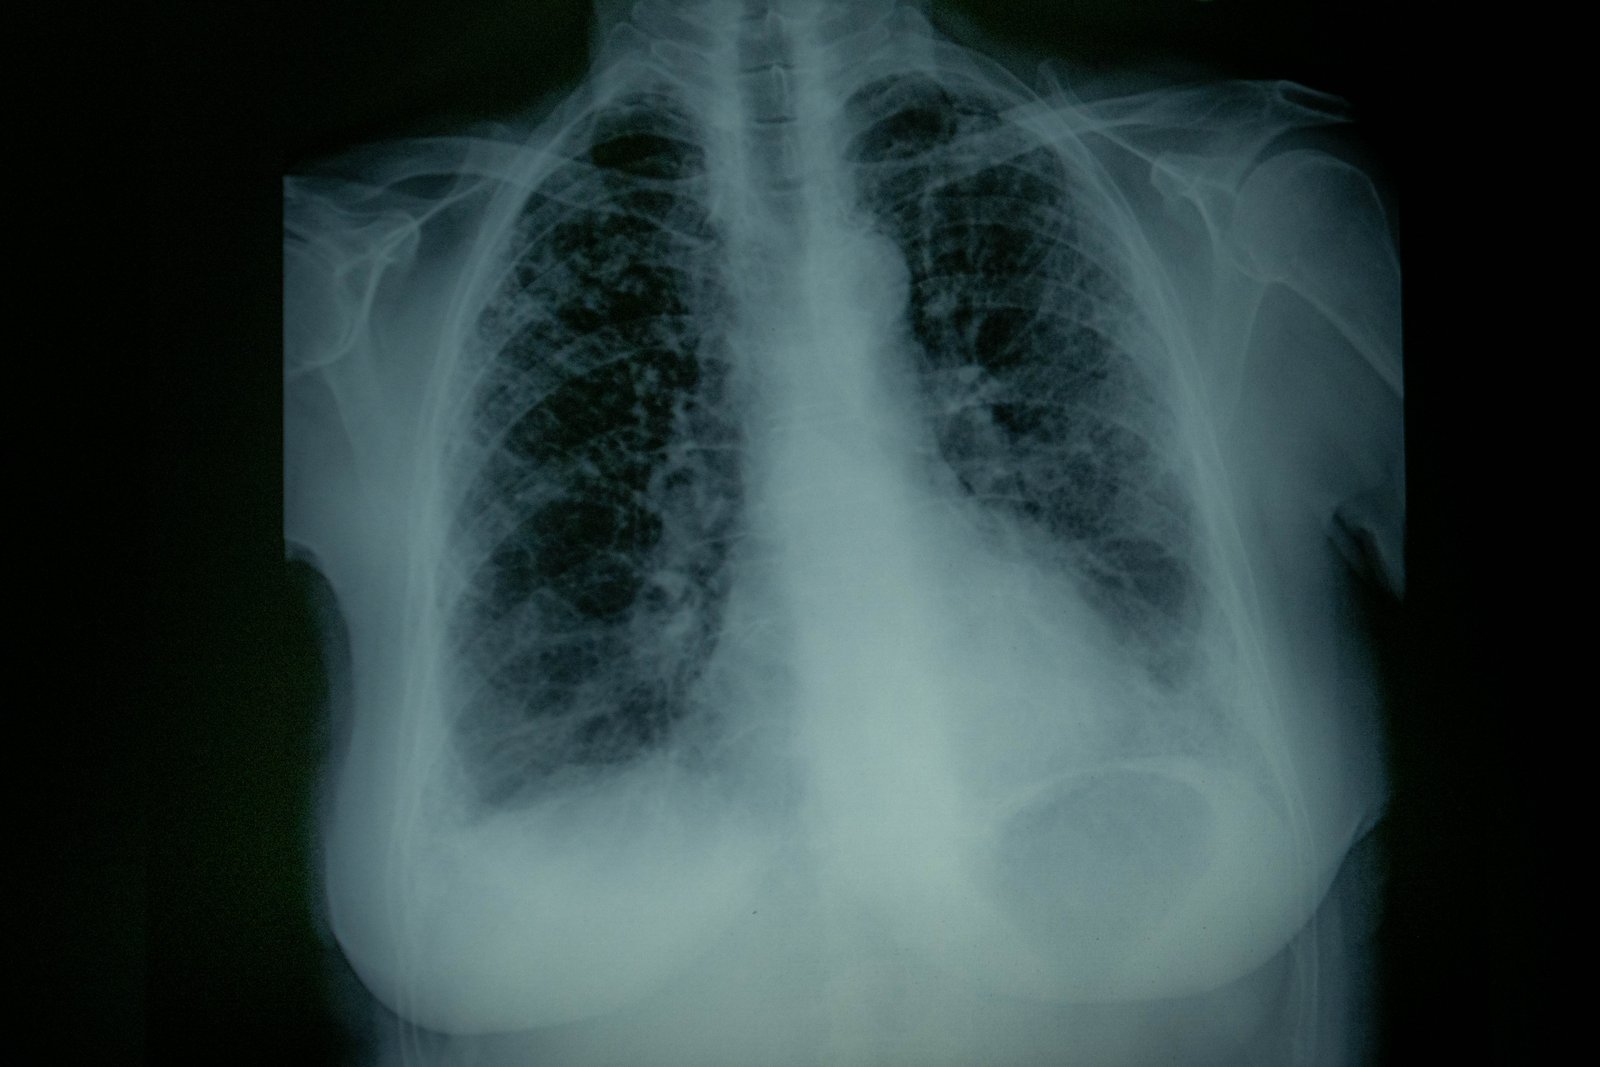

In the Anthropocene, our historical time that scientists suggest may be marked by the presence of chicken bones everywhere, factory farms have surged past the environmental safety thresholds established by experts. 11 billion chickens, 142 million pigs, 76 million bovines, 62 million sheep, 12 million goats: this is the population of invisible animals farmed in Europe yearly, that live and die on the (dis)assembly line. Factory farming is recognised as one of the top-most polluting industries worldwide in 2024, generating nearly 15% of total greenhouse gas emissions. Its impact on immediate surroundings is under-investigated. Noise, smell, air toxicity, chronic disease, water pollution: factory farms project negative externalities that hit neighboring communities first, often transforming local ecologies and endangering health and welfare. Residents across Europe endure an often daily barrage of invasive smells and gases. Gardening, drying clothes outdoors, or just opening a window become a burden. Visits dwindle. Mental health deteriorates. Homes plummet in value, leaving residents trapped. When air quality gets worse, residents often suffer from breathing difficulties, headaches, nausea, persistent cough, sometimes their eyes burn. Hydrogen sulphide, particulate pollution, ammonia, volatile organic compounds: farms release a number of externalities that make people sick in the short and long run, causing flu-like symptoms or triggering a development and deterioration of pathologies. Released in the atmosphere, ammonia turns into PM2.5, a group1 carcinogenic substance with estimated premature linked mortality of 253,000 cases yearly in Europe alone. Increasing evidence points to higher cancer rates in regions dense with large animal farming. In a time of increasingly frequent extreme novel epidemics and pandemics factory farms have become dangerous pathogenic breeding grounds. They have been linked to outbreaks of influenza strains like H1N1 swine flu and the H5N1 avian flu, diseases like African Swine Fever and Q-fever, jumping from animals to humans. Research linking higher incidence and severity of COVID-19 in these regions further compounds the issue. Many local communities across Europe are struggling in response to the rising local cost of factory farming, in terms of environmental damage, social welfare, and loss of life.